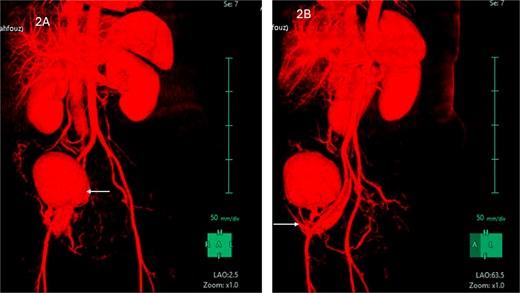

The MRI showed a large right iliac fossa extraperitoneal soft tissue mass, measuring 8.3 × 2.2 × 8.4 cm. The mass shows intermediate T2, low T1, and marked diffusion restriction. Dynamic imaging shows avid early contrast enhancement with retention of contrast in delayed imaging. The original spleen was in its normal place. The uterus showed multiple small intramural and subserosal fibroids with a low T2 signal, and an isointense T1 signal with no diffusion restriction or suspicious enhancement (Fig. 3).

MRI abdomen signifying the mass and its location, extent in both views (Arrow points at the mass).